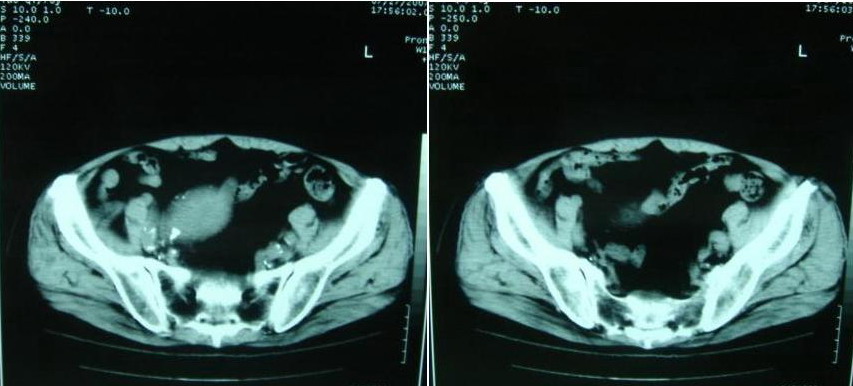

以下是引用借我一双慧眼在2007-8-29 16:24:00的发言:[br]典型腹主动脉瘤累及双侧髂总动脉

以下是引用快乐男生在2007-8-29 16:45:00的发言:[br]腹主动脉及右髂总动脉大范围的管径增粗,[br]管壁多发的钙化,[br]并见真假腔(双腔征),假腔可见附壁血栓.[br]考虑腹主动脉夹层动脉瘤 .建议增强或mri